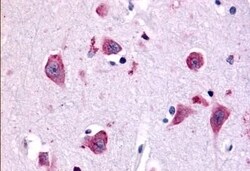

TAOK1 Polyclonal Antibody for IHC (P)

| Immunohistochemistry (Paraffin) | |

| Synthetic 16 amino acid peptide from internal region of human TAOK1. | |